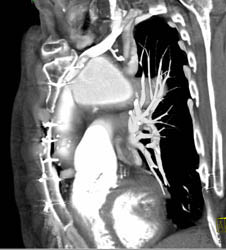

Plaque in LAD